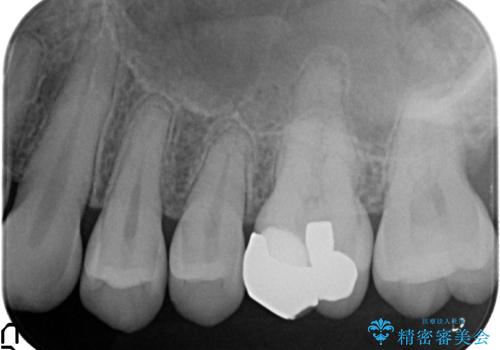

- 他院にて左上6番目の歯の神経が死んでいるといわれたので診て欲しいといらっしゃった方の症例です。

診査の結果左上6は失活していたため、根管治療を行った後にオールセラミッククラウンによる補綴を行いました。